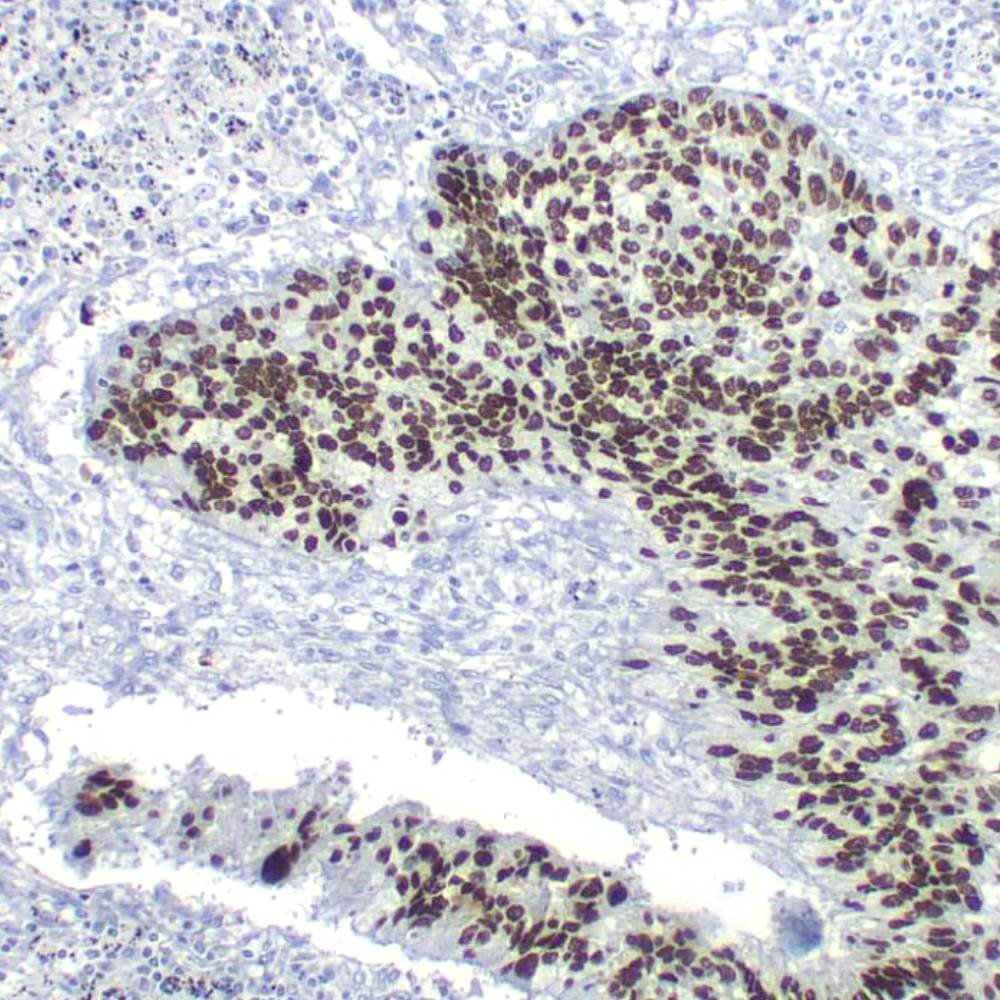

The Ki-67 protein is a nuclear protein doublet, 345-395 kDa, playing a pivotal role in maintaining cell proliferation. In diagnostic histopathology and cell biology, the antibody has proven valuable for the demonstration of the Ki-67 antigen in normal and neoplastic cells, for example in soft-tissue sarcoma, prostatic adenocarcinoma, and breast carcinoma. The Ki-67 has been confirmed as a very powerful single prognostic factor for overall survival, with highly proliferative cases showing a much poorer outcome than tumors with low proliferation. In breast cancer, the proliferative index measured by Ki-67 immunoreactivity has both prognostic and predictive value.